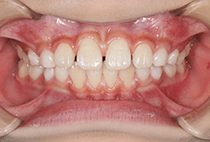

20代女性の患者さま。

八重歯の見た目が気になってご来院されましたが、実は顎の痛みや開口障害など、顎関節症の症状もありました。

そのため、かみ合わせと顎関節症の治療を同時に行ったにもかかわらず、2年間で治療が終了。

かみ合わせが整い咬筋の過緊張も改善しました。咬筋の肥大も治ってフェイスラインがすっきりしました。

最終的には美しい歯並びと、安定した痛みのないかみ合わせが実現しました。

八重歯が気になる

叢生、顎関節症、開口障害

20代女性

矯正治療2年

24回

唇側矯正

矯正:1,161,600円+毎月調整量:6,050円

しっかり前歯を下げるために、インプラントアンカーを使用してコントロールしました。

かみ合わせが整うと咬筋の過緊張が改善。

過緊張による筋肉肥大も改善しフェイスラインもすっきりしました。